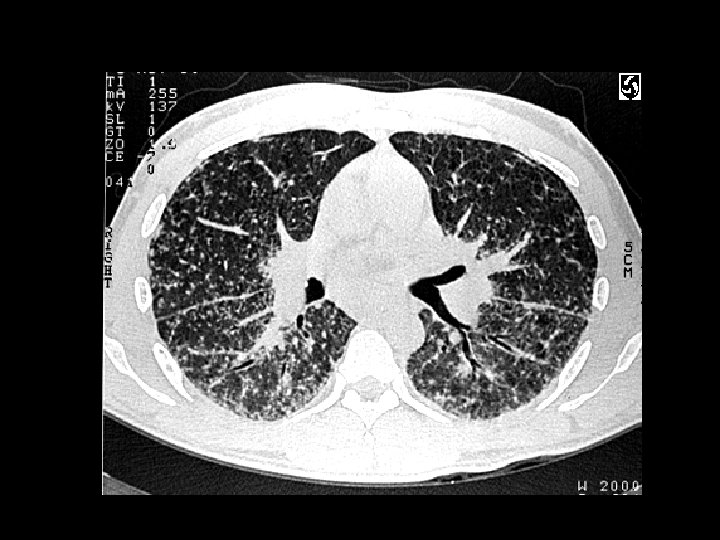

Lymphangioleiomyamatosis (LAM) • Findings: – hyperinflation with a reticular-nodular pattern – multiple thin-walled cysts • Rare dx of young women • present w/SOB, ptx, and chylous effusion • progressively fatal • ddx: – eosinophilic granuloma